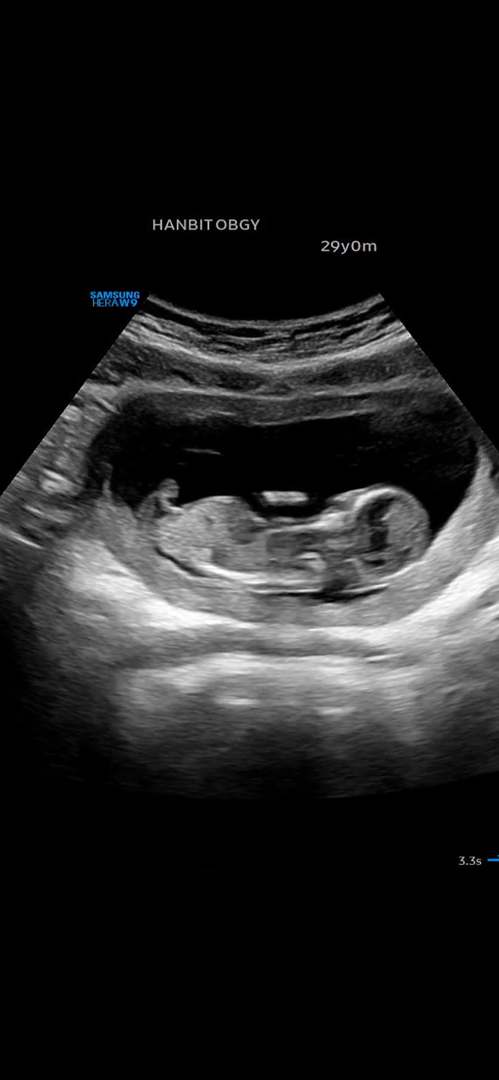

12주 각도법 한번봐주세요!

둘째라서 너무 궁금하네요ㅠㅠ 각도법 봐주시고 부턱드려요!!